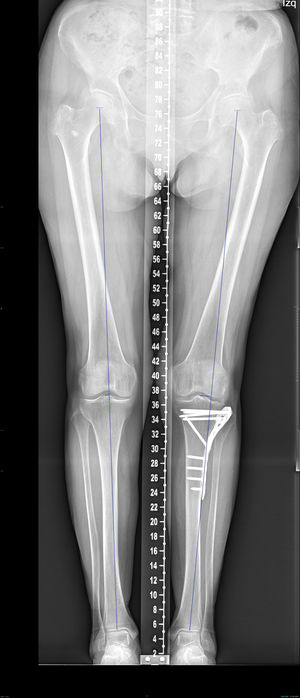

Deviation in millimetres of the load axis relative to the contralateral limb, the medial proximal tibial angle (MPTA) of both limbs, and the difference in degrees between them were analysed using telemetry (Fig. 2).

In the teleradiology analysis, the difference in the mean axis deviation from the contralateral leg was 12mm. The mean difference in MPTA was −1.1 degrees.

The mean step measured on CT was 3.6mm (SD: 1.9mm). The mean area measured on CT was 17.57cm2 (SD: 6.1cm2). The mean slope was 12.3 degrees (SD: 5.3 degrees).